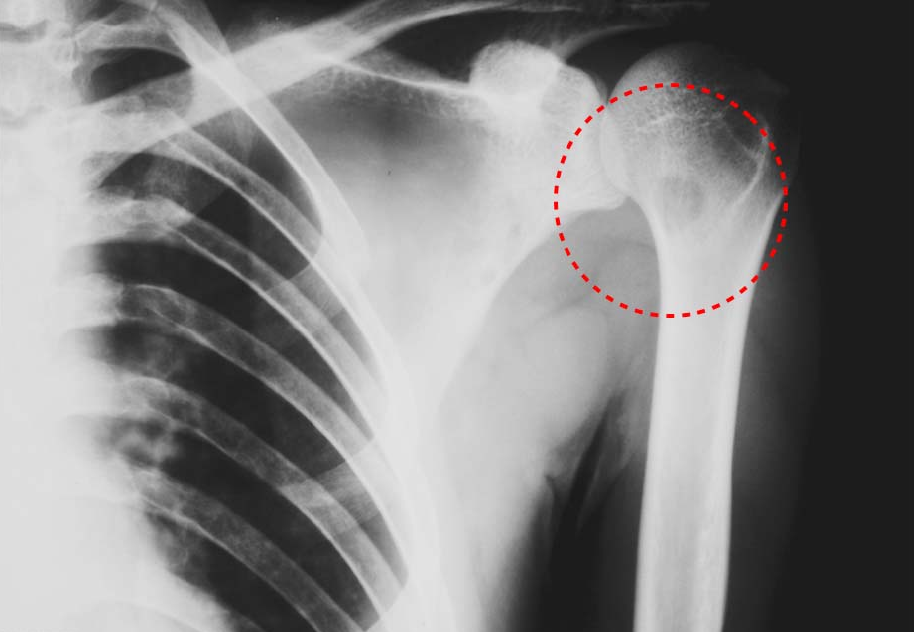

Figure4